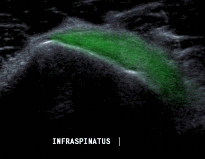

- Siêu âm gân cơ dưới gai và gân cơ tròn bé Tư thế: lòng bàn tay áp vào vai đối diện

Kỹ thuật: thực hiện các lát cắt sau khớp ổ chảo cánh tay, gân cơ dưới gai nằm ngay sau gân cơ trên gai, gai xương vai là mốc giải phẫu khảo sát phần cơ, gân cơ tròn bé nằm tiếp phía sau gân cơ dưới gai.

Hình 2.32. Hình ảnh siêu âm khảo sát cơ dưới gai112.